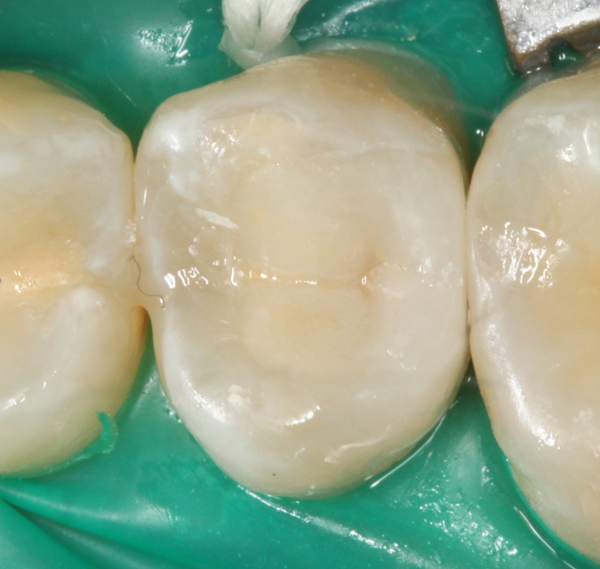

Unmittelbar nach dem Einkleben der Vollkeramikteilkrone (e.max Press) mit Variolink II A1 fotografiert: